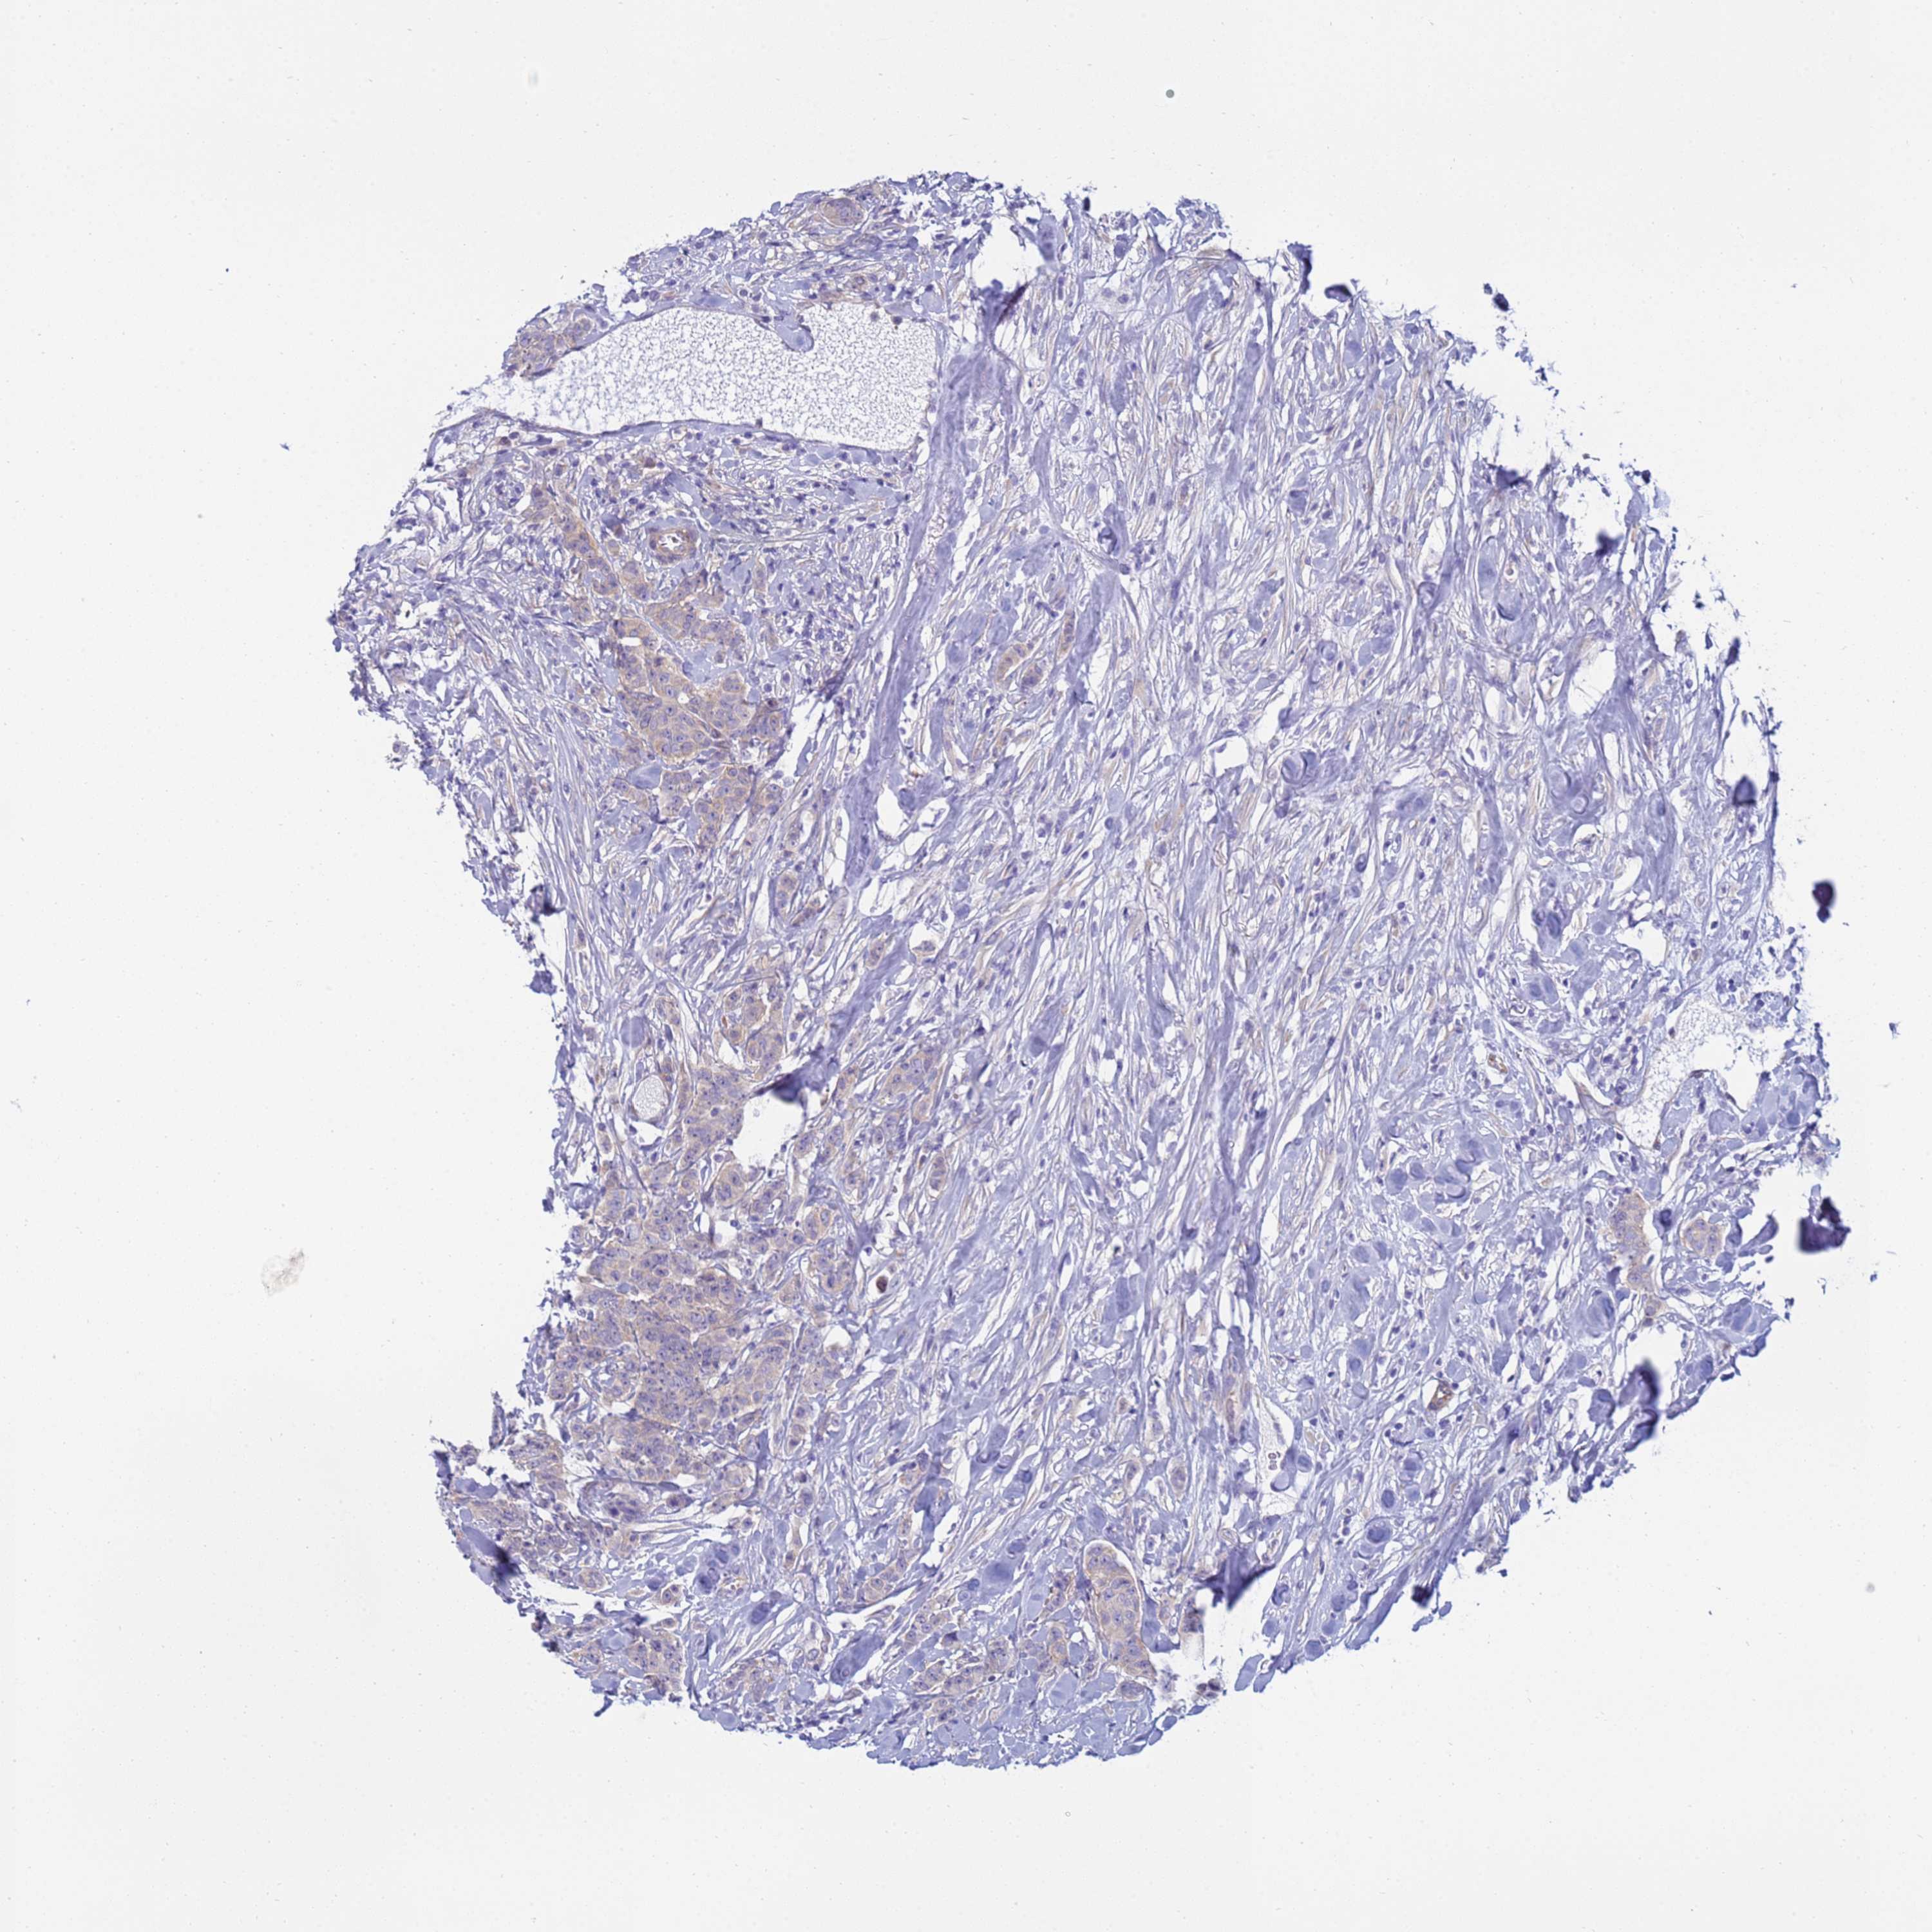

CANCER BREAST CANCER Show tissue menu

Breast cancer

Human cancer